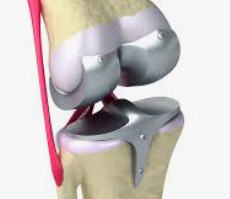

인공 관절 수술은 관절의 퇴행성 변화, 외상, 또는 다른 질환으로 인해 손상된 관절을 인공적인 재료로 만든 관절로 교체하는 의료 절차입니다. 이 수술은 주로 무릎, 고관절, 어깨 관절 등에 적용되며, 환자의 삶의 질을 향상시키고 통증을 감소시키는 데 목적이 있습니다.

인공 관절 수술의 종류는 크게 두 가지로 나뉩니다: 전치환술과 부분치환술입니다. 전치환술은 손상된 관절 전체를 인공 관절로 교체하는 방법이며, 부분치환술은 손상된 관절의 일부만을 교체하는 방법입니다. 환자의 상태와 필요에 따라 적절한 수술 방법이 선택됩니다.

전치환술은 관절의 변형이 심하거나 손상 부위가 넓은 경우에 주로 사용됩니다. 이 수술은 관절의 안쪽과 바깥쪽 모두를 인공 관절로 바꿔줌으로써, 통증을 줄이고 관절의 기능을 회복시키는 데 도움을 줍니다.

반면, 부분치환술은 관절의 손상이 비교적 제한적인 경우에 적합합니다. 이 수술은 절개 부위가 작고 회복이 빠르며, 무릎 운동 범위의 제한이 적다는 장점이 있습니다. 특히, 연골 내측만 손상된 경우나 십자인대 기능이 정상인 경우에 시행됩니다.